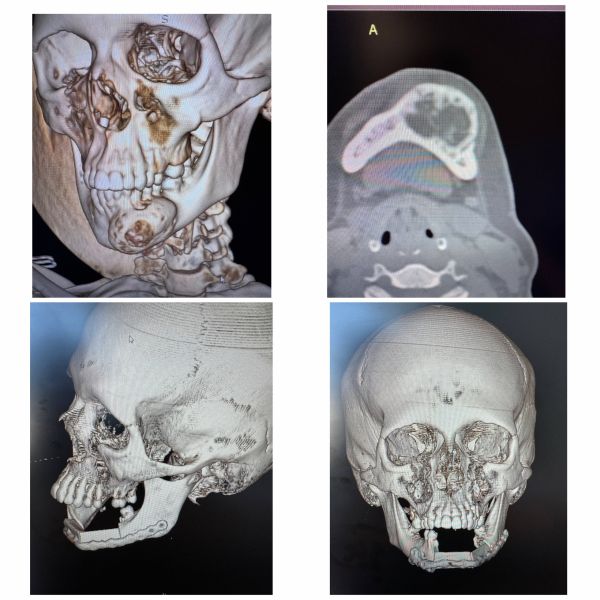

Уфимские хирурги успешно прооперировали пациентку с онкологией нижней челюсти

Врачи не только удалили новообразование, но и сразу же восстановили утраченный фрагмент челюсти с помощью собственной малоберцовой кости.

Челюсть буквально, как конструктор, собирали по 3D-шаблонам. Операция прошла успешно, женщину в скором времени выпишут домой.